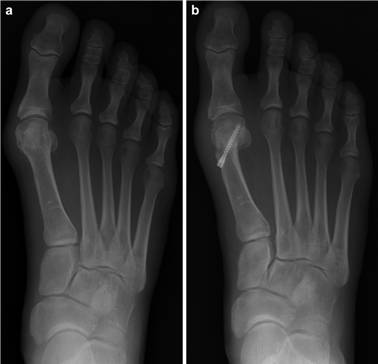

The Modified Chevron Osteotomy

The modified distal Chevron osteotomy is a powerful tool for mild to moderate hallux valgus. A medial longitudinal incision is made centered over the first MTP joint. Dissection is carried down to the joint capsule, taking care to protect the dorsal medial cutaneous nerve. A midline or L-shaped capsulotomy is performed, exposing the medial eminence. The medial eminence is resected parallel to the medial border of the foot, preserving the sagittal groove to avoid disrupting the articular surface.

A V-shaped osteotomy is then created in the metatarsal neck with an apex angle of approximately 60 degrees. The apex is positioned centrally within the metatarsal head, and the limbs exit dorsally and plantarly. The capital fragment is translated laterally by 30-50% of the metatarsal shaft width. If the DMAA is increased, a medial closing wedge can be incorporated into the osteotomy. The osteotomy is provisionally stabilized with a Kirschner wire, and definitive fixation is achieved using one or two headless compression screws directed from dorsal-proximal to plantar-distal. The medial capsule is then imbricated to correct the soft-tissue imbalance, and the skin is closed in layers.

The Lapidus Arthrodesis (First TMT Fusion)

For severe deformities or hypermobility, the Lapidus procedure provides robust stabilization of the medial column. A dorsal or medial incision is utilized over the first TMT joint. The extensor hallucis longus (EHL) is retracted dorsally, and the tibialis anterior tendon is identified and protected at its insertion on the medial cuneiform and first metatarsal base. The TMT joint capsule is incised, and the joint is thoroughly debrided of all articular cartilage using a combination of osteotomes, curettes, and a high-speed burr.

To achieve multiplanar correction, the surgeon must address the sagittal, coronal, and transverse planes. The first metatarsal is plantarflexed to restore the longitudinal arch, rotated out of pronation to realign the sesamoids, and translated laterally to close the IMA. Subchondral drilling or feathering is performed to optimize the biological environment for fusion. Fixation is traditionally achieved with two or three crossed solid or cannulated screws (typically 3.5mm or 4.0mm). Recently, plantar or medial locking plates have gained immense popularity due to their superior biomechanical construct, allowing for earlier weight-bearing. Bone graft or orthobiologics may be packed into the arthrodesis site to stimulate osteogenesis.